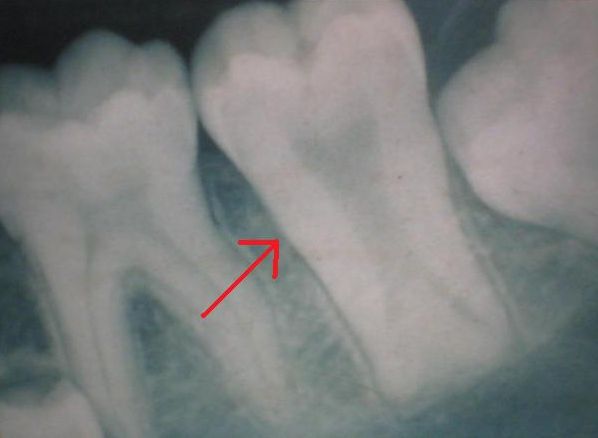

Тауродонтизм обнаруживается только благодаря рентгенографии. Его характеризует расширенная пульповая камера в форме прямоугольника. Тело зуба удлинено, корни и корневые каналы укорочены. При этом размер коронки остаётся нормальным.

Тауродонтизм на рентгенограмме

Бычий зуб необходимо отличать от наследственной патологии, при которой нарушается формирование дентина. У такого зуба на рентгенограмме отмечается большая пульповая камера и широкие апикальные (прикорневые) отверстия. Сами корни сформированы не полностью .